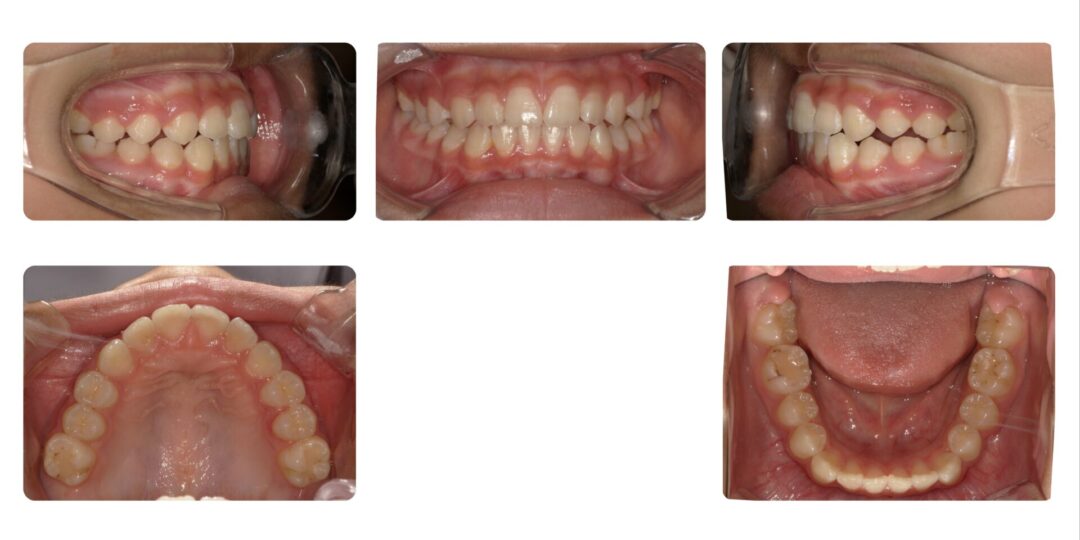

矯正治療前

初診時10歳

第一期治療 拡大ねじ付きバイオネーター

治療期間

1年7か月

治療費用

自由診療 基本料金¥330,000 処置料¥3,300